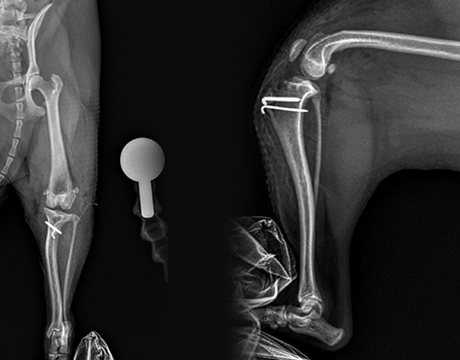

골절수술

- 요척골 단순골절

- 4살, 이탈리안그레이하운드

고난이도 상완골 원위부 골절

- IOHC, 상완골과골절

- 4개월 시추 2.6kg

고난이도 소형견 골절 수술